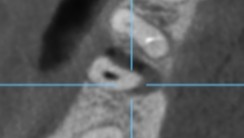

【CT画像 遠心根の近心側から舌側にかけて骨が消失 頬側骨は完全に消失しており歯根が露出している】

【赤矢印 骨消失部分】